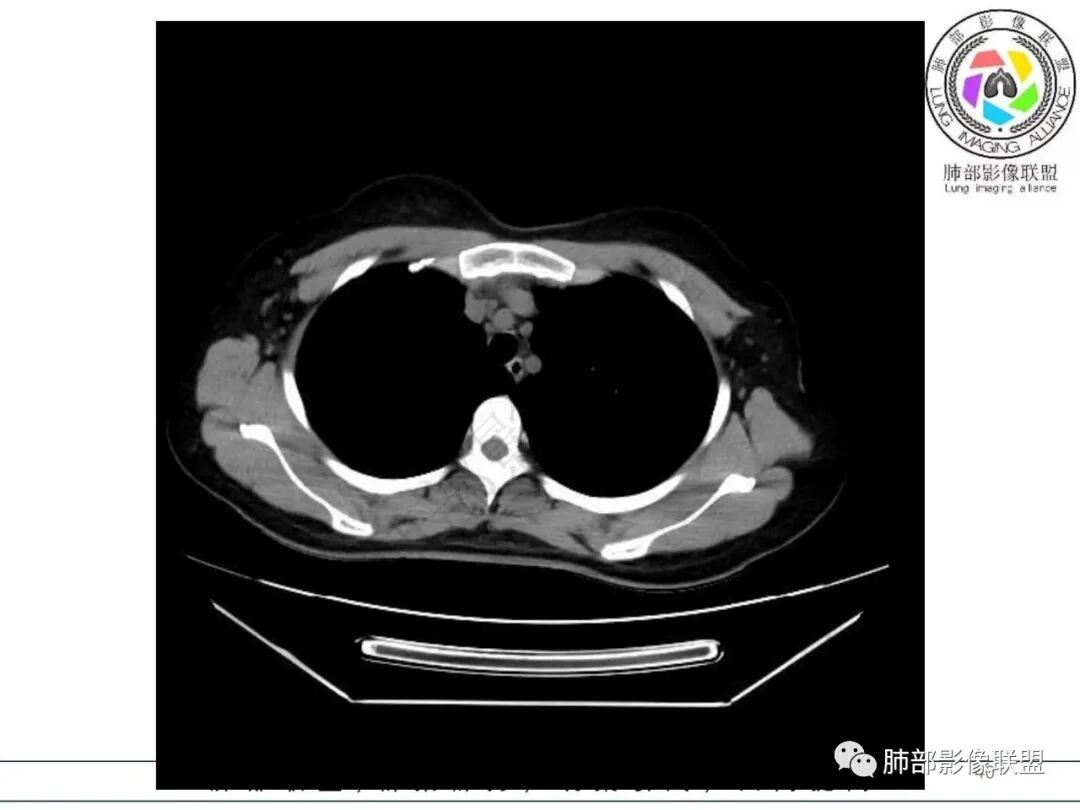

2.影像特征:右肺下叶局限性实变影伴晕征,边界不清,内部支气管尚通畅,实变区密实区边缘稍膨隆。符合炎性病灶特征。

偏密实区支气管显示欠佳,密度稍低区支气管显示,密实区边缘稍膨隆

内部支气管还算通畅

周围GGO边界不清